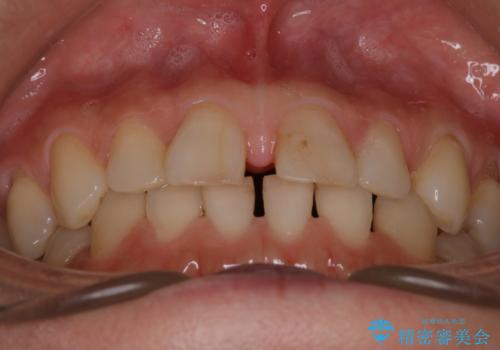

【審美装置】すきっ歯をワイヤー装置で治したい

- 前歯のすきっ歯が気になるということで来院されました。今回は抜歯はしないためワイヤー矯正かインビザライン矯正のどちらでも治療可能でしたが、患者さまのご希望により表のワイヤー装置にて治療をおこないました。

前歯に隙間がいくつかあったため、今回は上下でゴムかけを行いスペースを埋めるための力をかけて閉じました。もう少し早く終了する予定でしたが、ブラッシング不良による歯肉腫脹があり、一部スペースクローズに時間がかかりました。